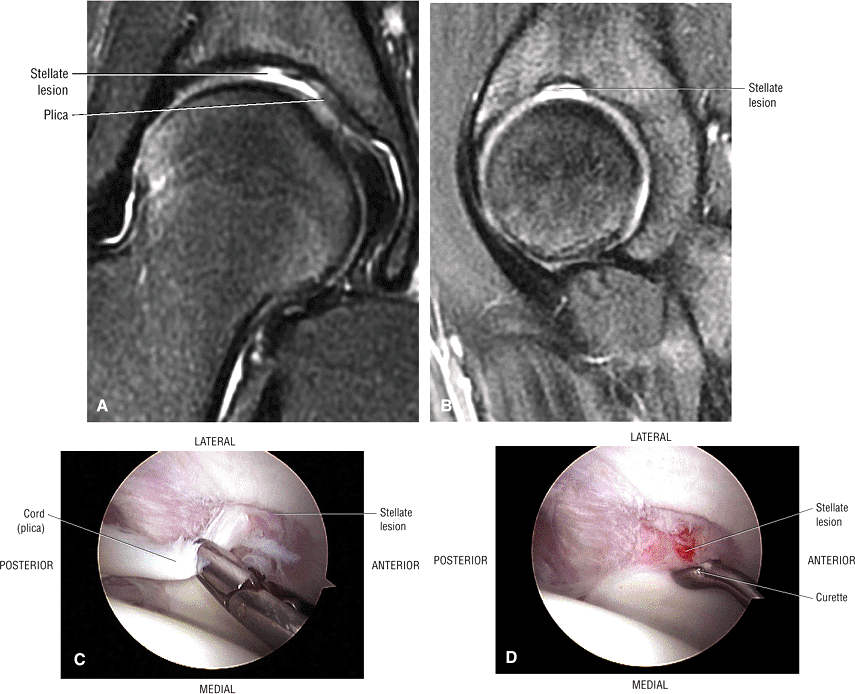

The stellate lesion or crease represents a normal bare area superior to the acetabular fossa.

FIGURE 3.51 ● (A) The stellate crease (arrows) is shown above the acetabular fossa (F) and within the lunate surface of the acetabulum. The stellate crease, (lesion) represents a bare area deficient in hyaline cartilage and not degeneration. Arthroscopically, this bare area may appear as an indentation. The femoral head (H) is indicated. Anterior is down and posterior is up. (B) The articular lunate surface of the acetabulum. The osseous acetabular rim is angled anteroinferior relative to the sagittal plane. The adult aperture angle is 17°.

|